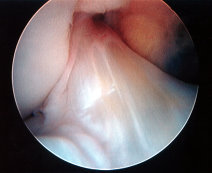

ACL Rupture

Exclude combined ACL+ Meniscal Detachment